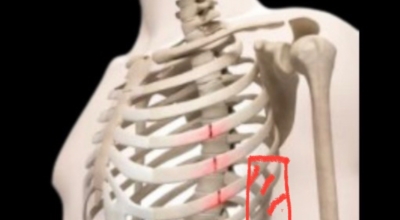

왼쪽 옆구리 통증 - 근육 긴장

많은 운동, 외상 또는 부적절한 자세는 왼쪽 옆구리 부위의 복근 또는 척추주위 근육에 영향을 미치는 근육 긴장을 초래할 수 있습니다. 이러한 유형의 왼쪽 옆구리 통증은 일반적으로 날카롭고 움직이면 악화되며 휴식을 취하면 완화됩니다.